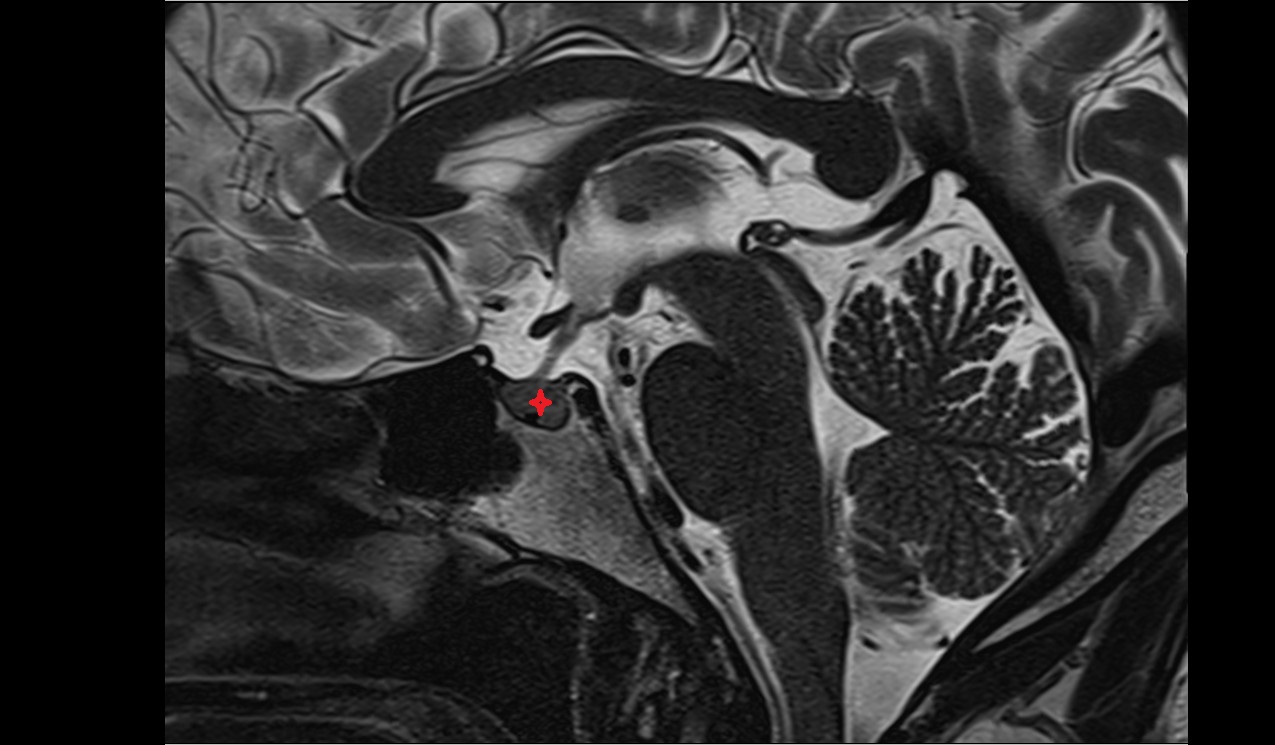

- Uterus

- Body of uterus

- Fundus of uterus

- Cervix of uterus

- Isthmus of uterus

- Vagina

- Fornix of the vagina

- Endometrium of uterus

- Myometrium of uterus

- Perimetrium of uterus

- Junctional zone of uterus